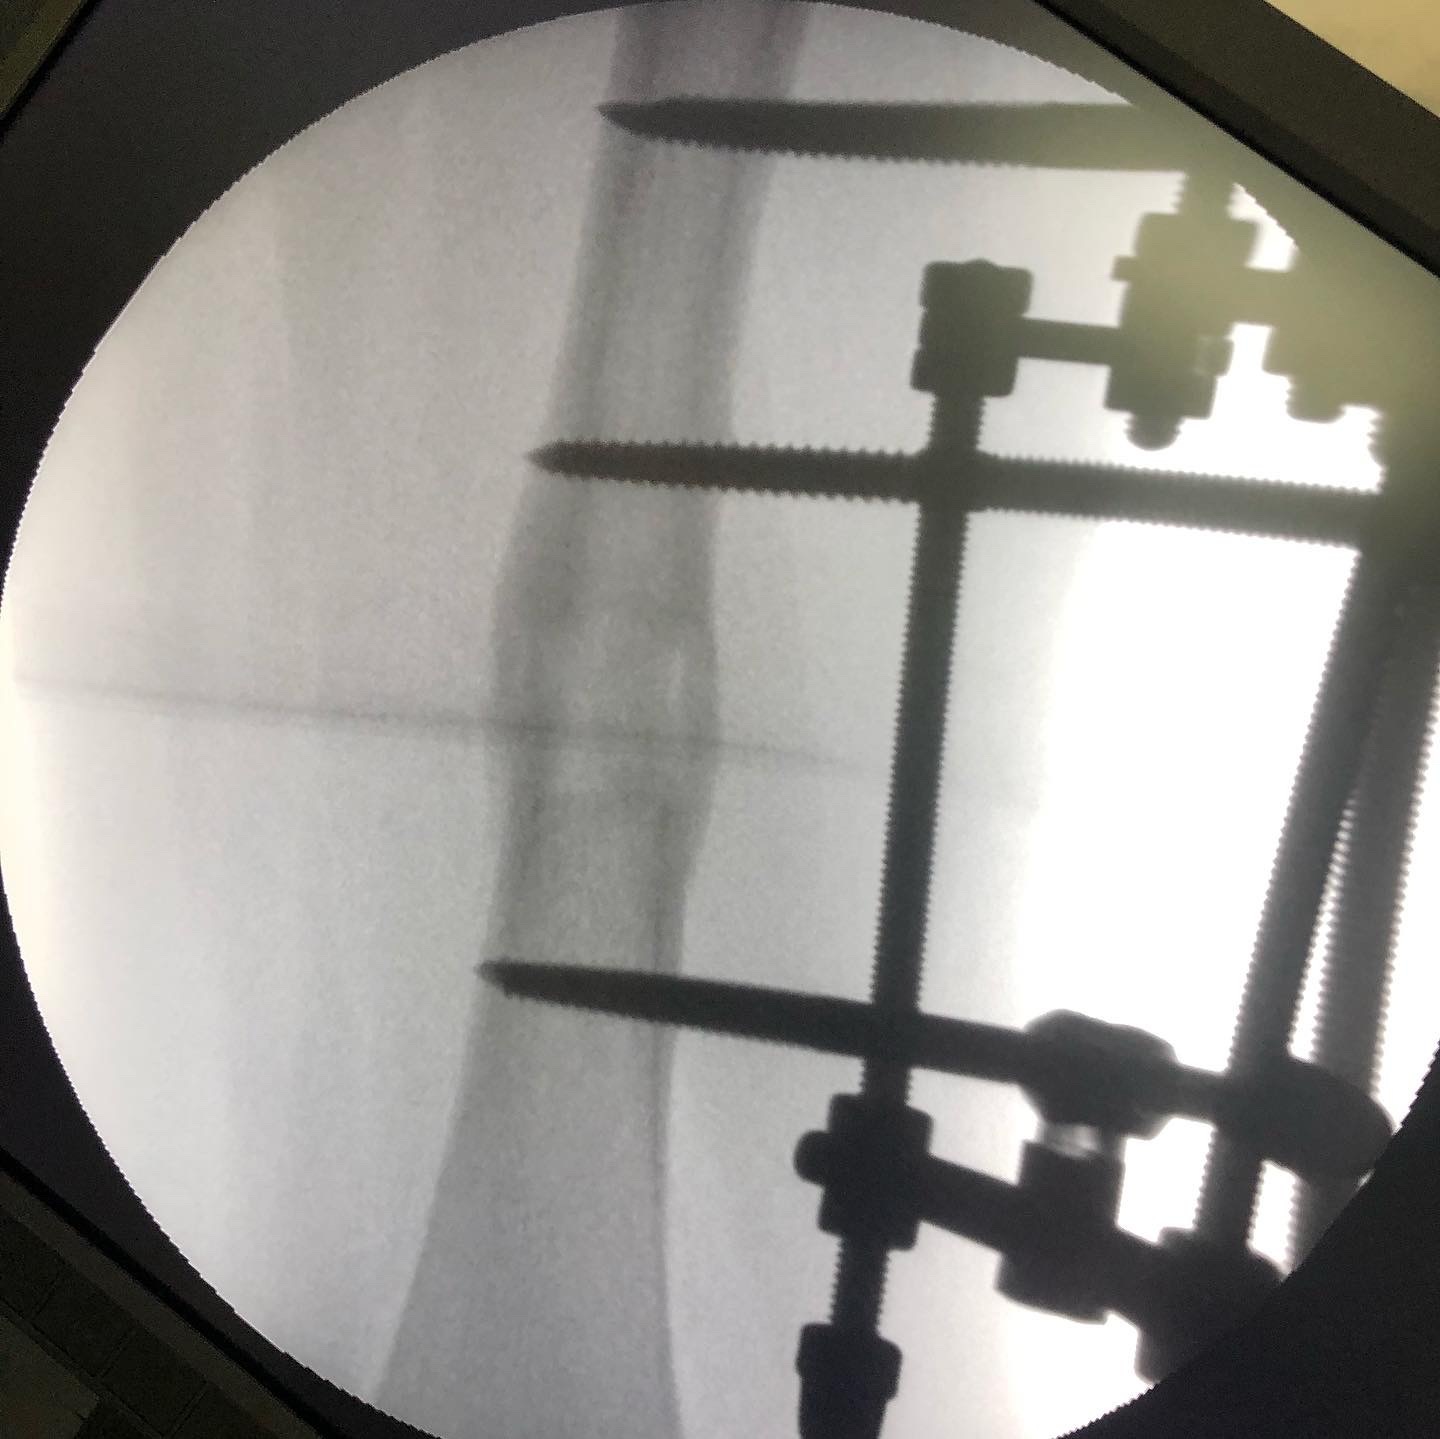

Выполнено: операция по коррекции шеечно-диафизарных углов с одновременным удлинением правого бедра на 2 см.

Фиксация АВФ без разрезов кожи (с проколов).

Срок лечения — 3 месяца.